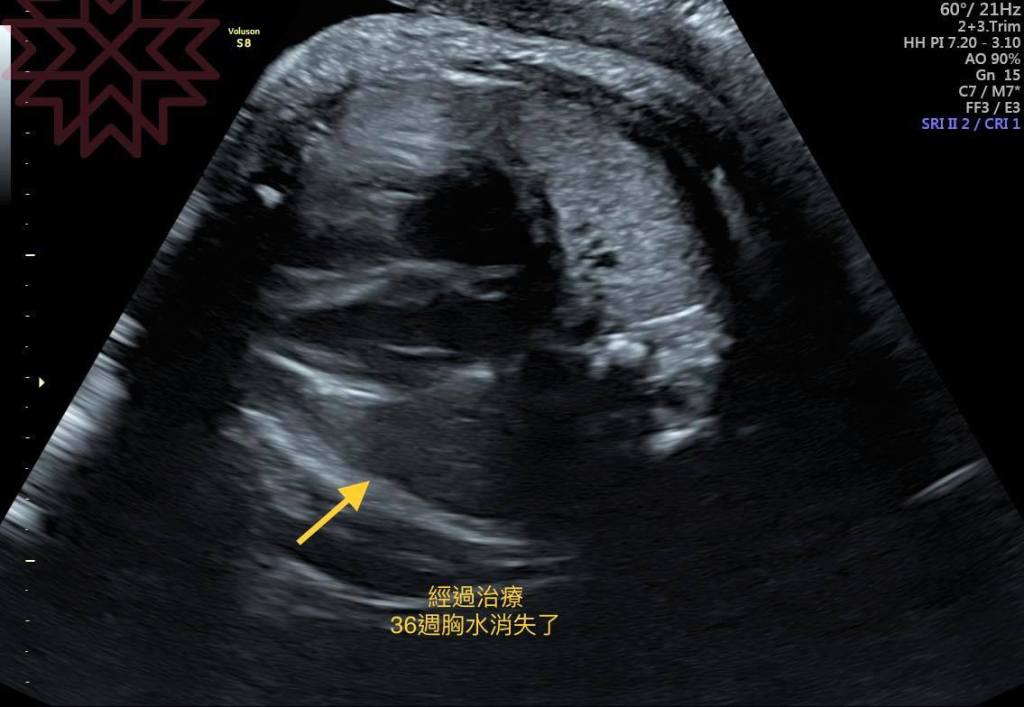

經過了兩個星期密集的胎兒治療和追蹤

我們歷經了一次又一次的追蹤治療跟等待

終於

到了36週

胸水全部消失

我知道

我們過關了